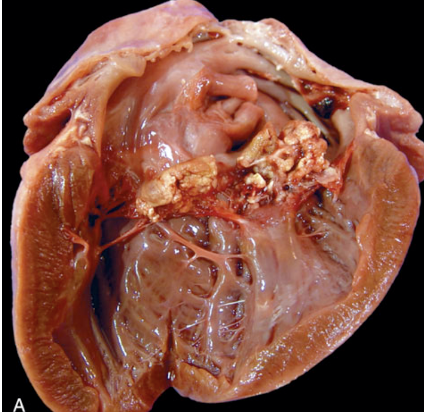

What is affecting this heart? note the rough irregular nodules around the heart valves.

vegetative valvular endocarditis